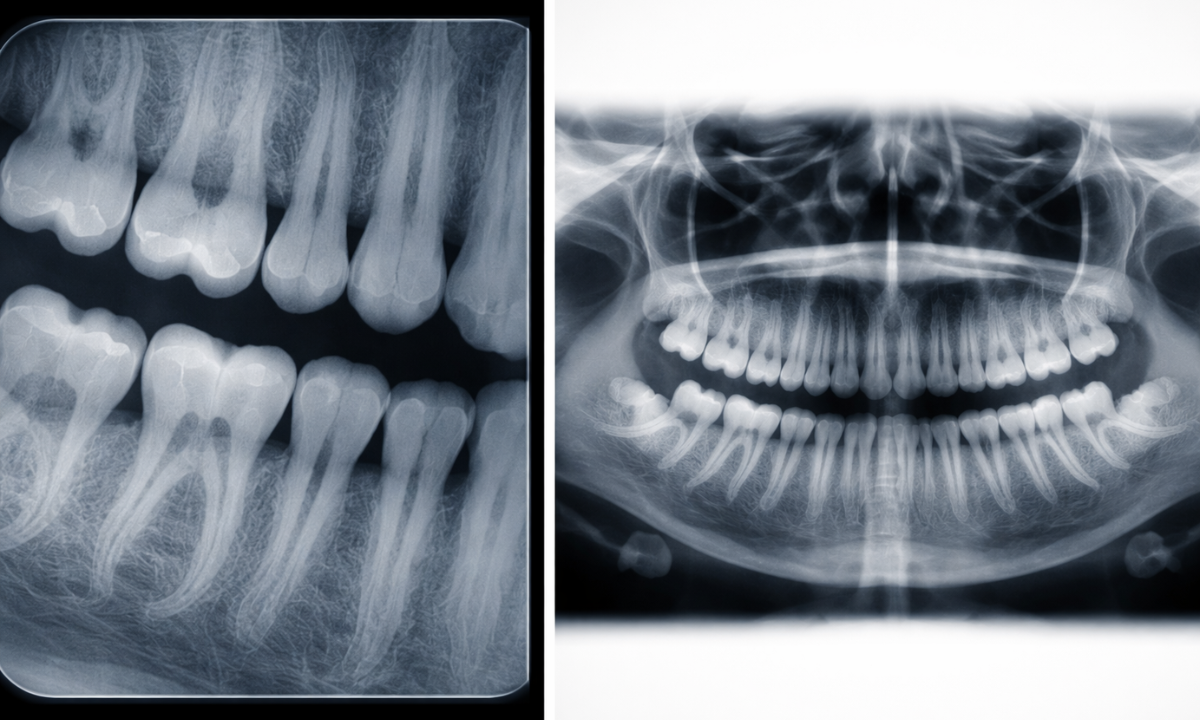

Dental Radiography

A dental X-ray operates on a much smaller scale but provides high-resolution images of the teeth and jawbone.

- Intraoral X-rays: The film is placed inside the mouth to detect cavities between teeth, check the health of the tooth root, and monitor the surrounding bone level.

- Extraoral X-rays: The film is outside the mouth. This is used to track jaw growth, identify impacted wisdom teeth, or visualize the temporomandibular joint (TMJ).

Dental X-rays use significantly lower radiation doses than medical X-rays.

They are an essential part of routine dental checkups to identify issues like cysts or abscesses that are invisible during a visual exam.